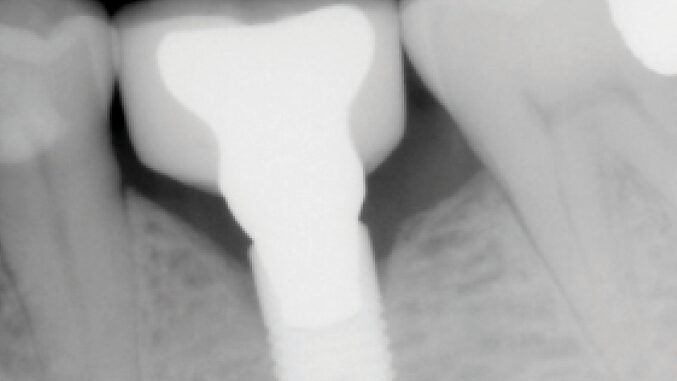

Fracture of dental implants with internal, conical connections: A case series

Deporter-Fig_1D alternate text for this image

Abstract Purpose: Fracture of dental implants, though uncommon, presents significant clinical consequences. The case reports presented explore the fracture of four dental implants in three patients. All were of the Astra Osseospeed® design with internal conical connections. All fractured at the level of the prosthetic connection, providing insight on potential contributing factors. Methods: Three patients all received … Read more